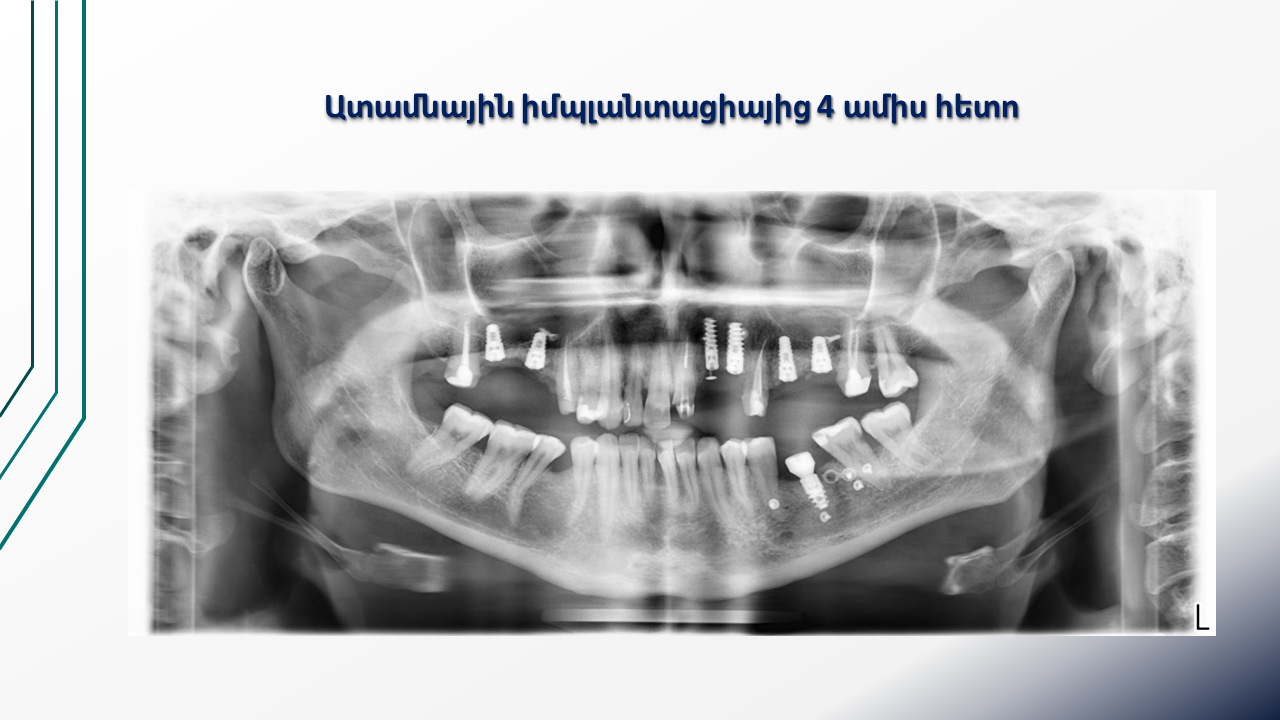

Titanium Mesh for Alveolar Ridge Reconstruction (16.03.2024 )

Clinical case of guided bone regeneration using a patient-specific 3D-printed titanium mesh in a pregnant patient. Multistage protocol with bone augmentation, implant placement, and soft tissue management. Presented by Dr. Levon Galstyan and Dr. Roza Hovhannisyan.